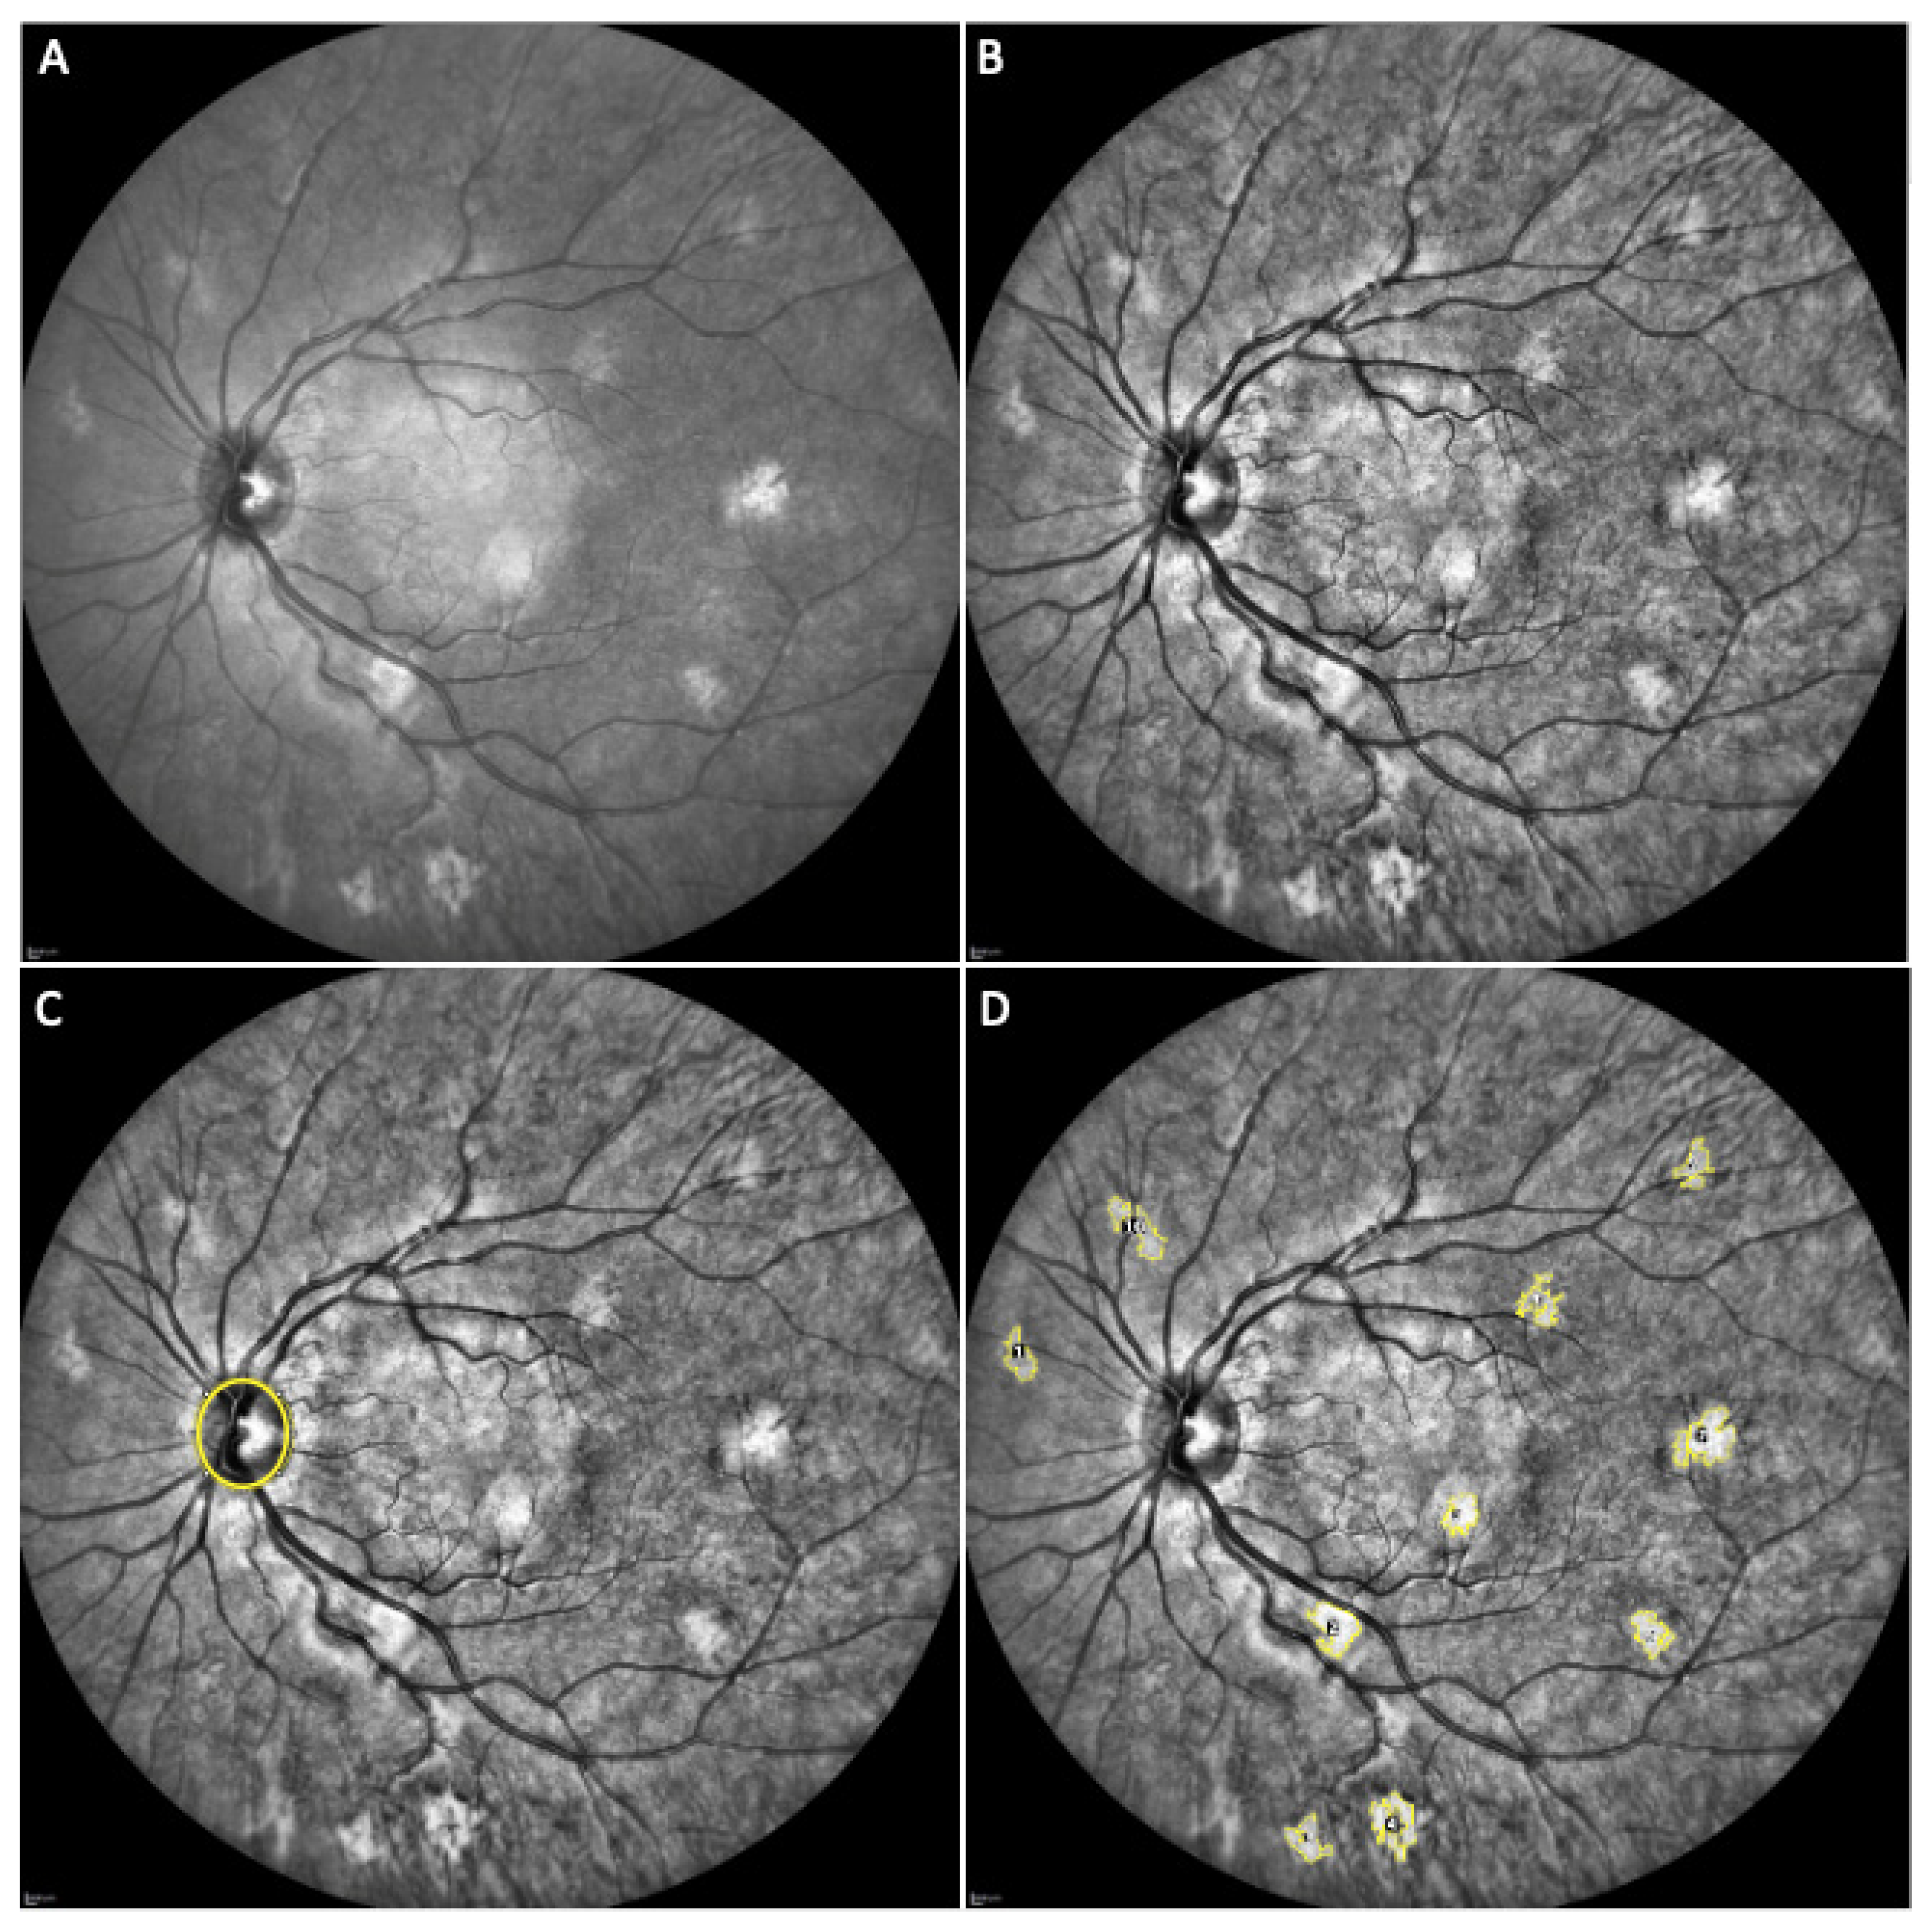

- Parrozzani, R.; Clementi, M.; Frizziero, L.; Miglionico, G.; Perrini, P.; Cavarzeran, F.; Kotsafti, O.; Comacchio, F.; Trevisson, E.; Convento, E.; et al. In vivo detection of Choroidal abnormalities related to NF1: Feasibility and comparison with standard NIH diagnostic criteria in pediatric patients. Investig. Ophthalmol. Vis. Sci. 2015, 56, 6036–6042. [Google Scholar] [CrossRef]

- Vagge, A.; Camicione, P.; Capris, C.; Sburlati, C.; Panarello, S.; Calevo, M.G.; Traverso, C.E.; Capris, P. Choroidal abnormalities in neurofibromatosis type 1 detected by near-infrared reflectance imaging in paediatric population. Acta Ophthalmol. 2015, 93, e667–e671. [Google Scholar] [CrossRef]

- Viola, F.; Villani, E.; Natacci, F.; Selicorni, A.; Melloni, G.; Vezzola, D.; Barteselli, G.; Mapelli, C.; Pirondini, C.; Ratiglia, R. Choroidal abnormalities detected by near-infrared reflectance imaging as a new diagnostic criterion for neurofibromatosis 1. Ophthalmology 2012, 119, 369–375. [Google Scholar] [CrossRef] [PubMed] [Green Version]

- Yasunari, T.; Shiraki, K.; Hattori, H.; Miki, T. Frequency of choroidal abnormalities in neurofibromatosis type 1. Lancet 2000, 356, 988–992. [Google Scholar] [CrossRef]

- Nakakura, S.; Shiraki, K.; Yasunari, T.; Hayashi, Y.; Ataka, S.; Kohno, T. Quantification and anatomic distribution of choroidal abnormalities in patients with type I neurofibromatosis. Graefe’s Arch. Clin. Exp. Ophthalmol. 2005, 243, 980–984. [Google Scholar] [CrossRef]